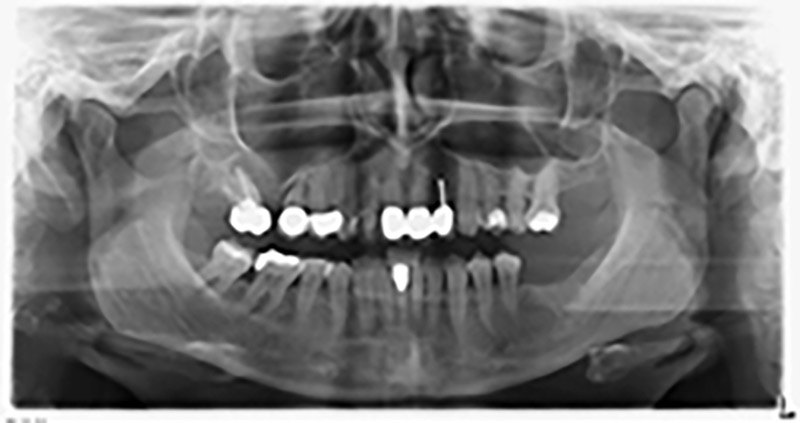

Etwa sechs Monate nach Extraktion der Zähne 16 und 14 wurde zur Planung und Risikominimierung eine digitale Volumentomografie (DVT, Planmeca) erstellt. Hierbei wurde deutlich, dass der Knochen sich nicht in der gewünschten Quantität regeneriert hat (Abb. 2 bis 7).